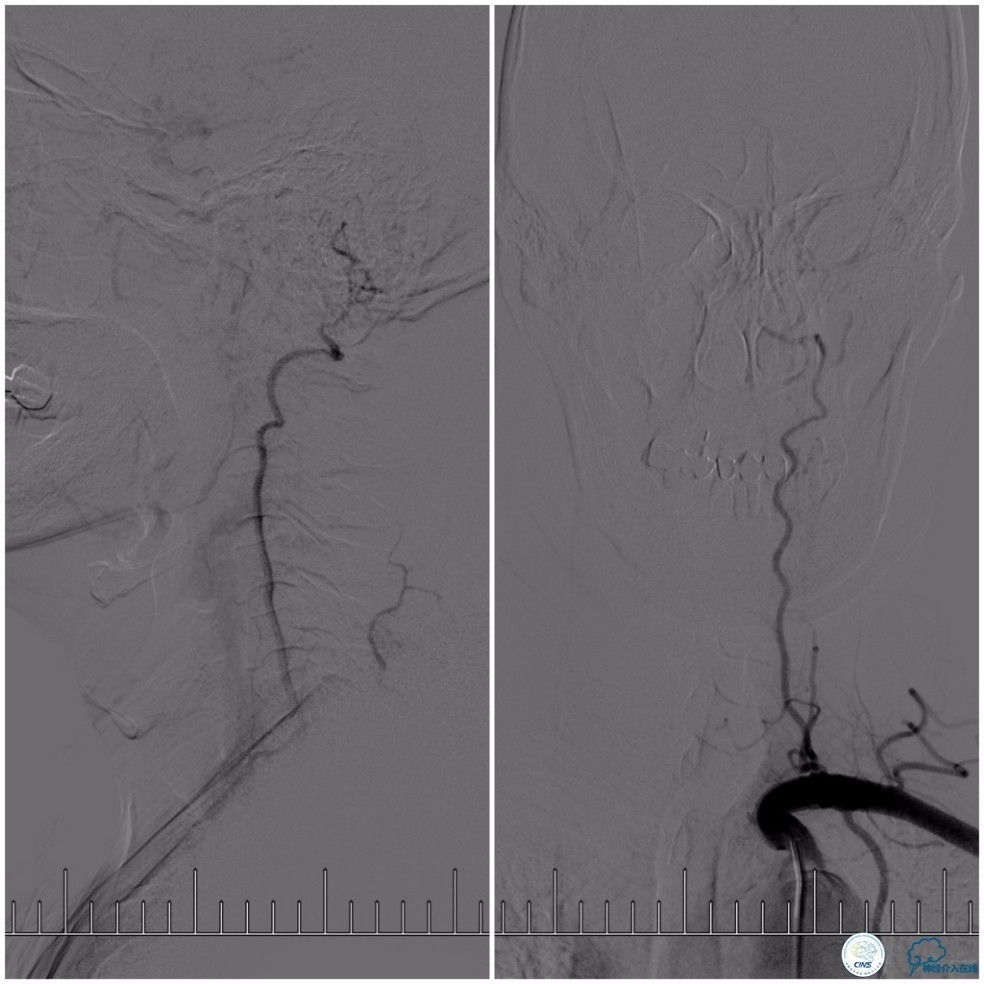

全麻下,右股动脉穿刺,因8F导引导管不能通过右椎动脉V1段,改用6F导引导管置于右椎动脉V2段,穿刺左股动脉放置5F导引导管用于栓塞动脉瘤入路。Transend微导丝(0.014″,300cm)通过基底动脉狭窄段,放置在右大脑后动脉P2段后选择Gateway球囊(2.0mm×15mm)先预扩狭窄(图10)。

图10

Wingspan支架(3.0mm× 20mm)系统到位后,经5F导引导管放置Echelon-10微导管至动脉瘤腔内,释放Wingspan支架,进行动脉瘤栓塞(图11)。

图11

沿Echelon-10微导管依次推入EV3 PC-3-6-3D 3mm×6cm、QC-3-6-3D 3mm×6cm、QC-2-6-3D 2mm×6cm、QC 1.5-2-HELIX 1.5mm×2cm四个弹簧圈进入动脉瘤腔内。造影显示动脉瘤腔填塞致密(图12)。

图12